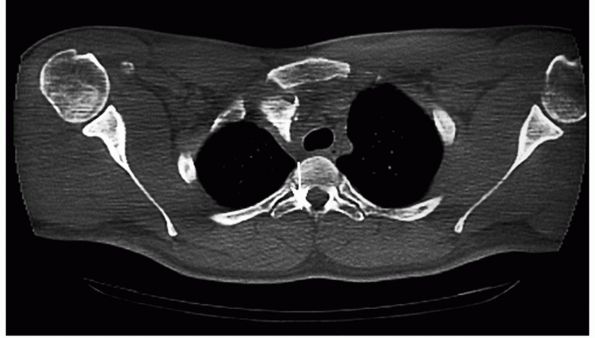

![]() |

FIGURE 40-2

Computed axial tomogram of a posterior SC joint dislocation that occurred when the driver’s chest impacted the steering wheel during a motor vehicle accident. The steering wheel was fractured from the driving column and the vehicle was totally destroyed. |